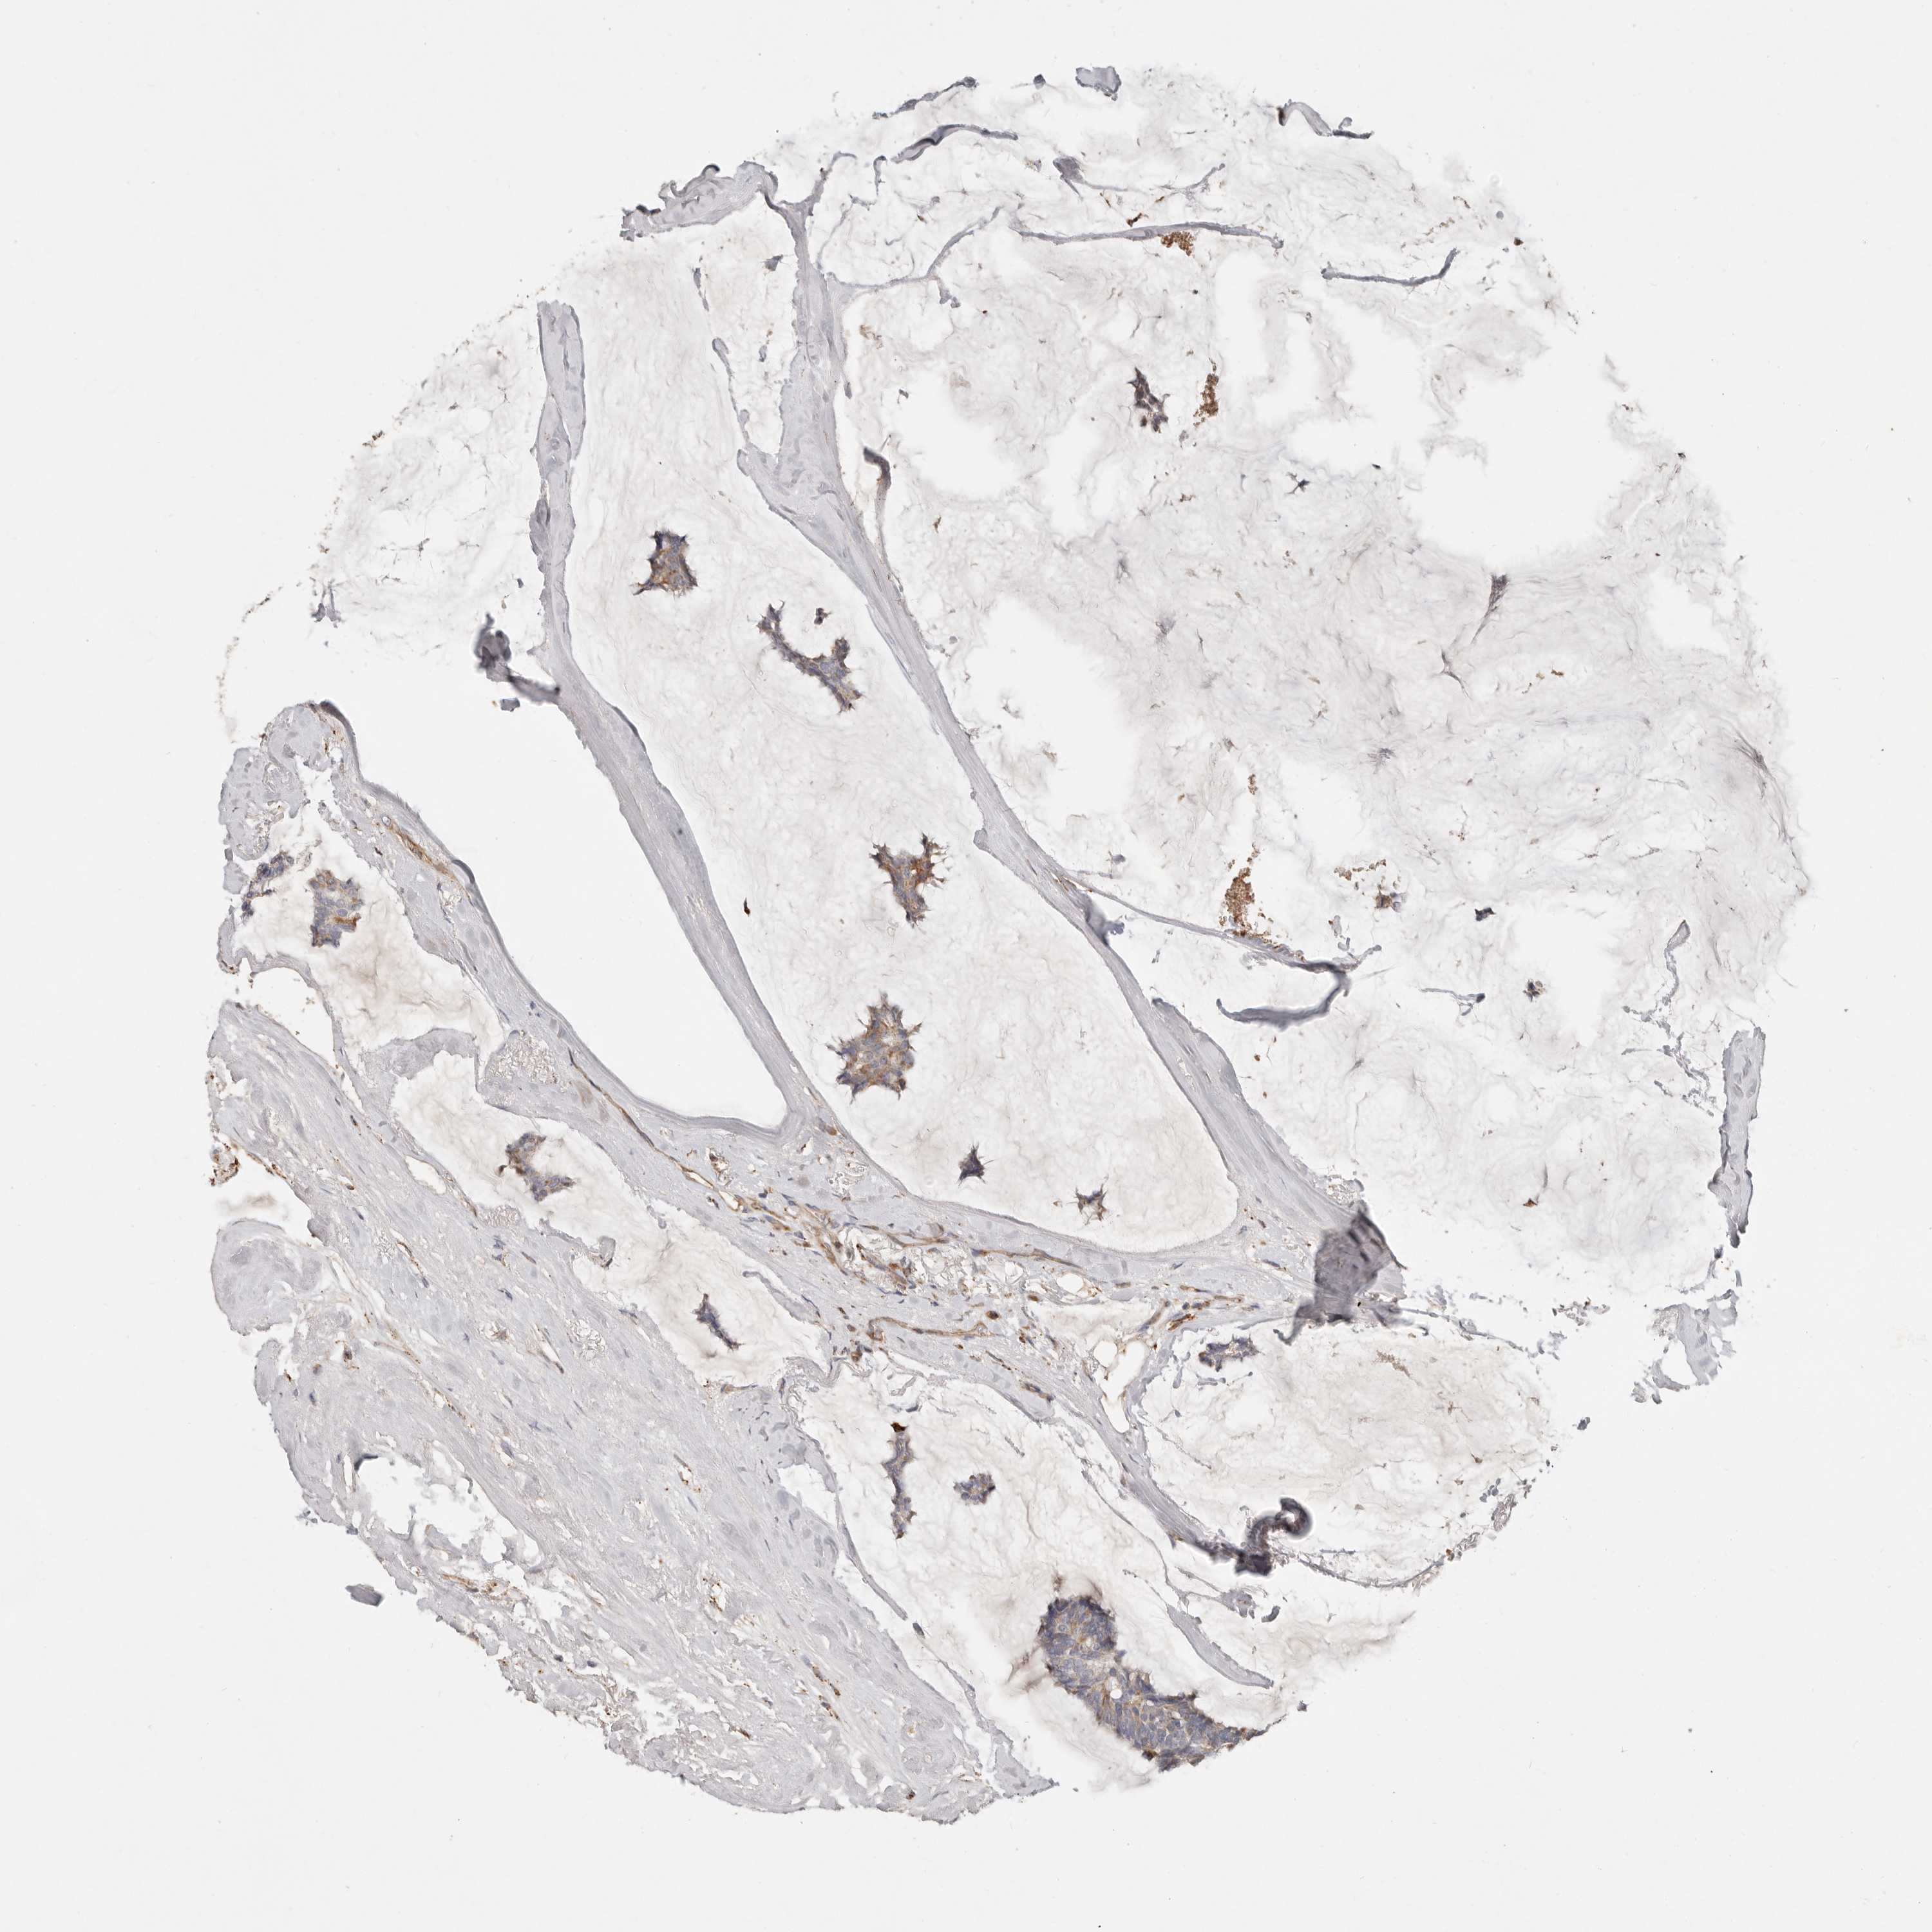

BRCA TCGA BRCA VALIDATION PROTEIN EXPRESSION